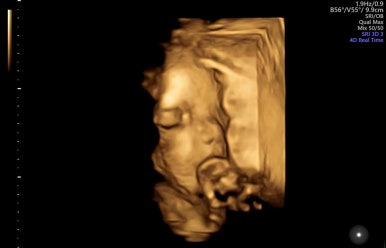

28주 1일

입체초음파로 태아의 얼굴을 볼 수 있는 시기이다!

제일 기다렸던 때이고, 다행히 태아 얼굴을 볼 수 있었다.